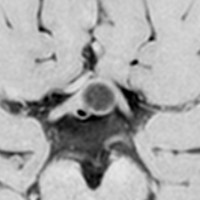

29歳の女性が高プロラクチン血症による月経不順で発症しました。視野検査では両耳側半盲が認められました。

手術所見では,多量のコレステリン結晶が流出しました。腫瘍実質は硬く正常下垂体との剥離はできませんでした。黄色肉芽種の可能性もあるので,あ全摘出にとどめて手術を終了しました。T2強調画像で黒い低信号の縁取りがあり内部に不均一なのう胞内容液が見えるのが特徴とも言えます。

3年後の画像です。腫瘍の再燃増大はありませあん。視野は正常化して,下垂体機能も正常化しホルモン補充はありません。